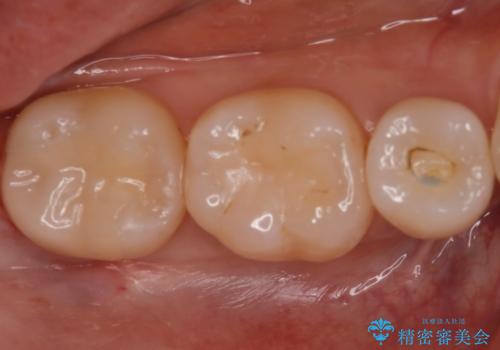

- 他院にて虫歯を指摘され、セカンドオピニオンを希望し当院へ来院されました。以前より磨きずらさと舌感の悪さは自覚していたそうです。清掃性、機能性に優れたセラミックインレーにて治療をすることとなりました。

レントゲンから昔詰めた保険の詰め物が入っていることが確認できました。詰め物と歯の隙間が虫歯になっていたためしっかり取り除き、適合の良いセラミックインレーを入れました。